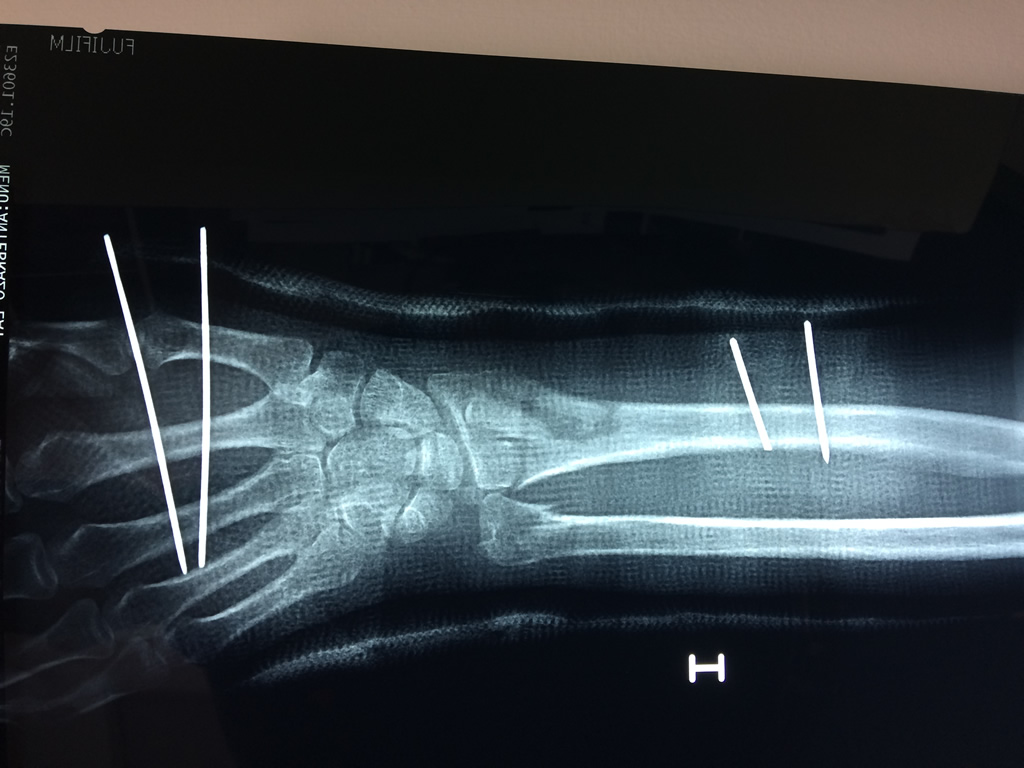

Cirugías de Calcaneo - Cirugías de Muñecas y Manos

Los procedimientos más comunes en cirugía de la mano son aquellos destinados a reparar traumatismos, incluyendo lesiones de tendones, nervios, vasos sanguíneos, y articulaciones; huesos fracturados; y quemaduras, cortes, y otros daños de la piel.